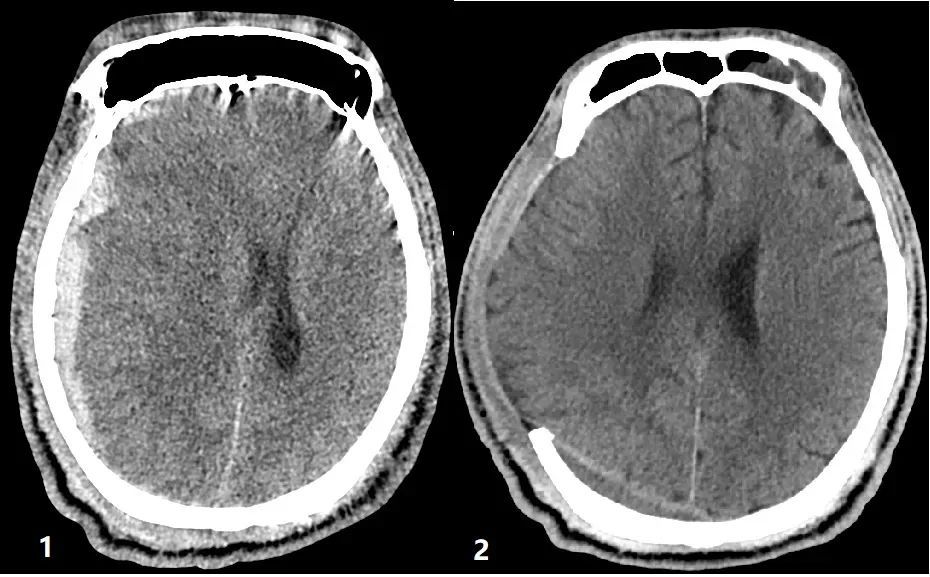

图片:手术前后头部CT对比

术后,患者被送往重症监护室,医护人员密切观察着各项生命体征和瞳孔变化,一夜平稳。第二天复查头部CT,颅内出血清除干净彻底,没有再次出血。第三天,患者苏醒并可以睁眼,还可以简单和医护人员交流。据悉,待患者病情稳定后,医院将开展针对性的中医调理和康复治疗,在医护人员的精心治疗下,患者逐步恢复。